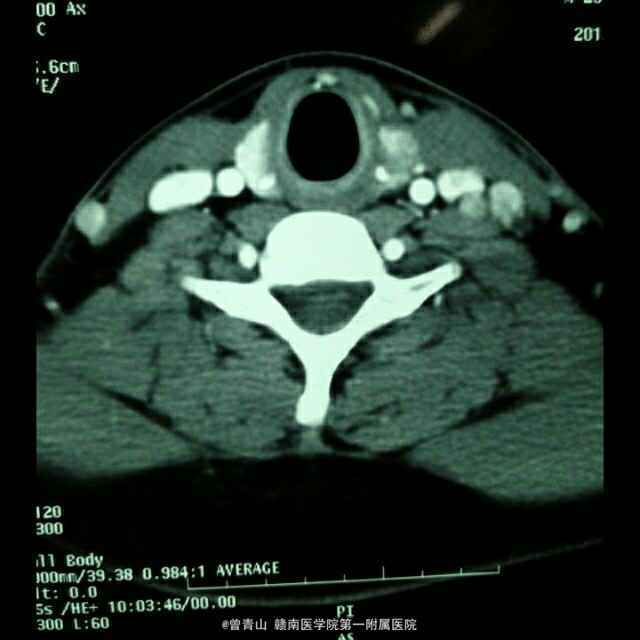

患者男性,20岁,因“咽部不适20天,发现颈部包块1天入院” 患者因咽部不适,吞咽异物感就诊于当地医院,一直给予针对慢性咽喉炎治疗,无明显效果。患者于昨日就诊于我科门诊,查体发现左侧甲状腺肿大,给予彩超检查发现左侧甲状腺肿物。

查体:心肺腹未见异常,口腔面膜充血,咽部见淋巴滤泡。甲状腺触诊发现左侧Ⅱ度肿大,边界不清,活动度尚可。 CT,彩超

诊断:甲状腺癌、慢性咽喉炎 治疗:手术方式~甲状腺左侧腺叶+峡部切除+喉返神经解剖术+中央区淋巴结清扫